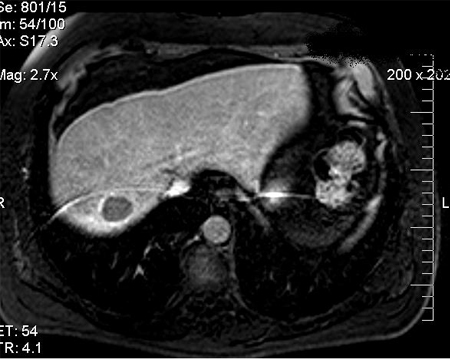

contrast MRI of abdomen

Test

If there is elevated alpha fetoprotein and/or abnormal ultrasound with focal liver lesion(s), then multiphasic CT or dynamic contrast-enhanced MRI of the abdomen should be ordered to confirm the diagnosis of hepatocellular carcinoma (HCC).[2][7][69]

The National Comprehensive Cancer Network (NCCN) suggests dynamic contrast-enhanced MRI (or CT) as an alternative to ultrasound for screening and surveillance if ultrasound is unable to detect nodules or if visualisation is poor.[2] The sensitivity of MRI of the abdomen for diagnosing HCC is 81%; specificity is 85%.[65]

MRI is superior to CT scan of the abdomen in differentiating dysplastic nodules, vascular lesions (haemangioma), and focal fat from HCC. However, one Cochrane review found that MRI may miss up to 16% of people with HCC, and 6% of patients without HCC may be treated unnecessarily.[71]

MRI is usually less readily available than CT, and the choice between the two modalities is typically centre-dependent.

Non-invasive diagnosis of HCC should be based on the Liver Imaging Reporting and Data System (LI-RADS) criteria.[2][62] ACR: Liver Imaging Reporting and Data System (LI-RADS®) Opens in new window

[Figure caption and citation for the preceding image starts]: MRI: hypervascularity on the arterial phaseFrom the personal collection of Badar Muneer MD, Florida Hospital Transplant Center, Orlando, FL; used with permission [Citation ends].